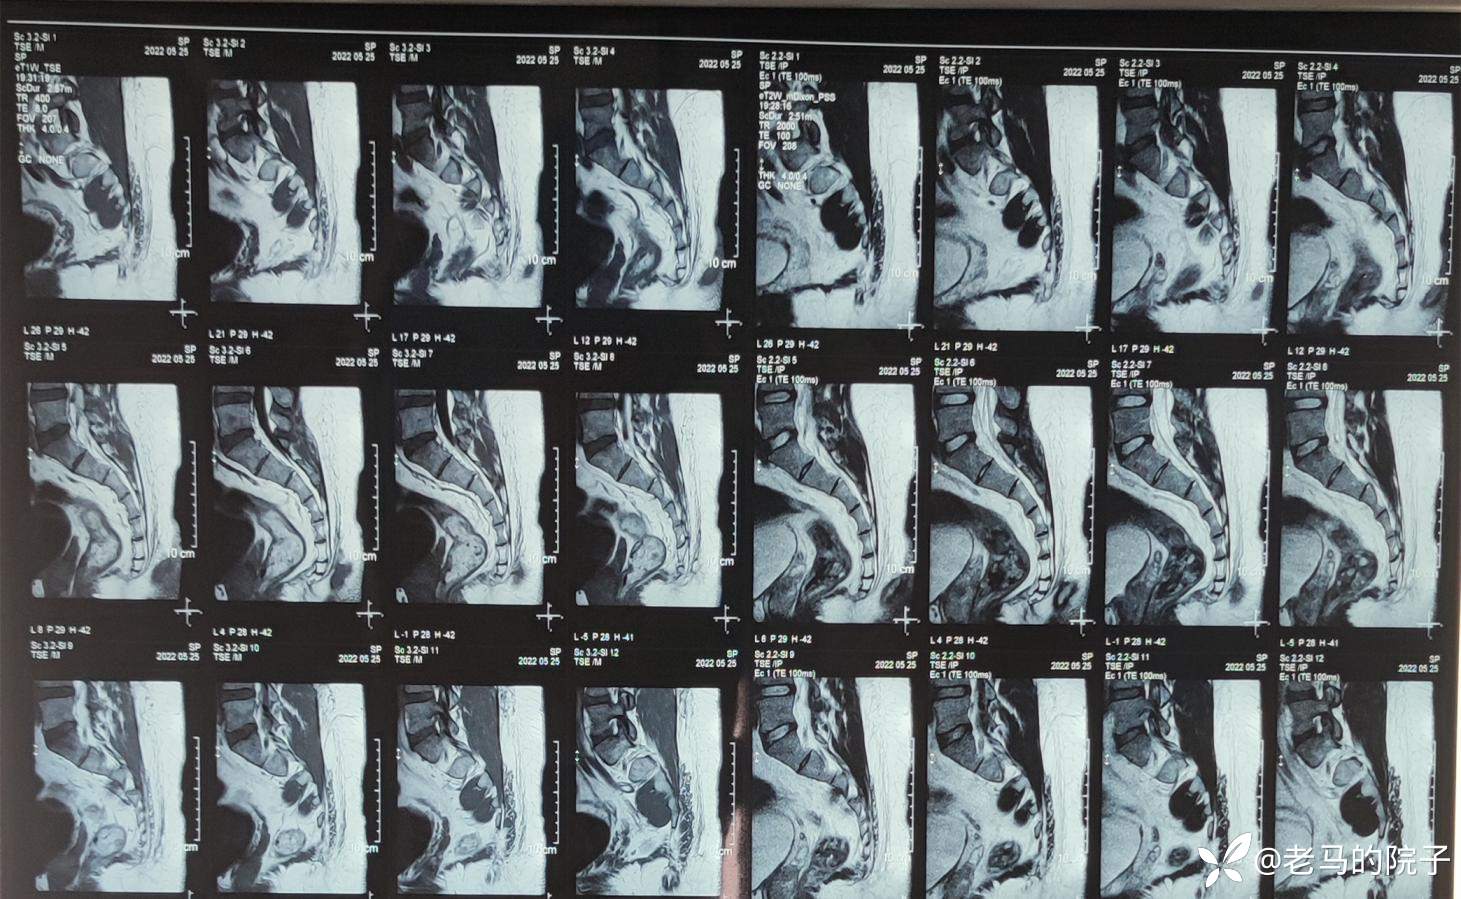

入院后查MRI见下图1、图2、图3

图1

图2

图3

MR影像报告单见下图

骶尾部核磁脂肪层内异常信号,未见与骶尾部神经有关系,未见骨质破坏